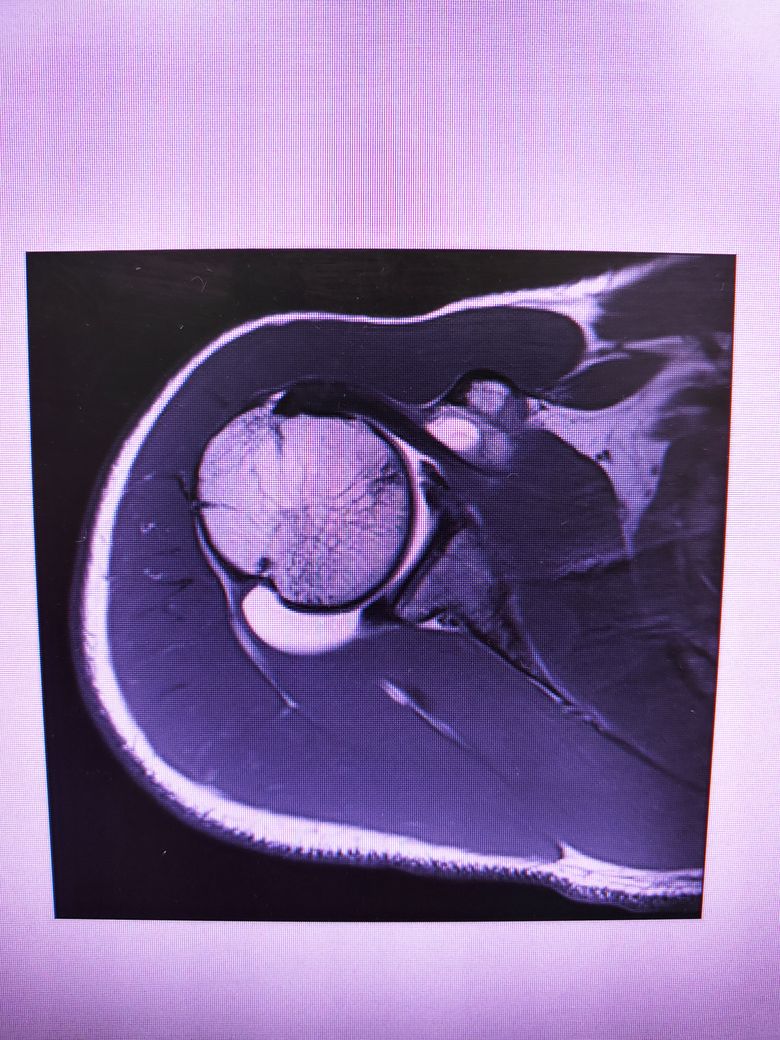

팔이 잡아당겨지는 사고 이후 통증이 지속되어

조영제 투입 후 mri 촬영을 하였습니다.

진단명은 상부관절와순파열(슬랩)이며

헬스와 같은 운동을 계속 하려면 수술이 필요하다 하였습니다.

슬랩이 맞나요? 맞다면 파열 진행 정도는 어느정도인지..

궁금합니다..최대한 사진 많이 올립니다 감사합니다..